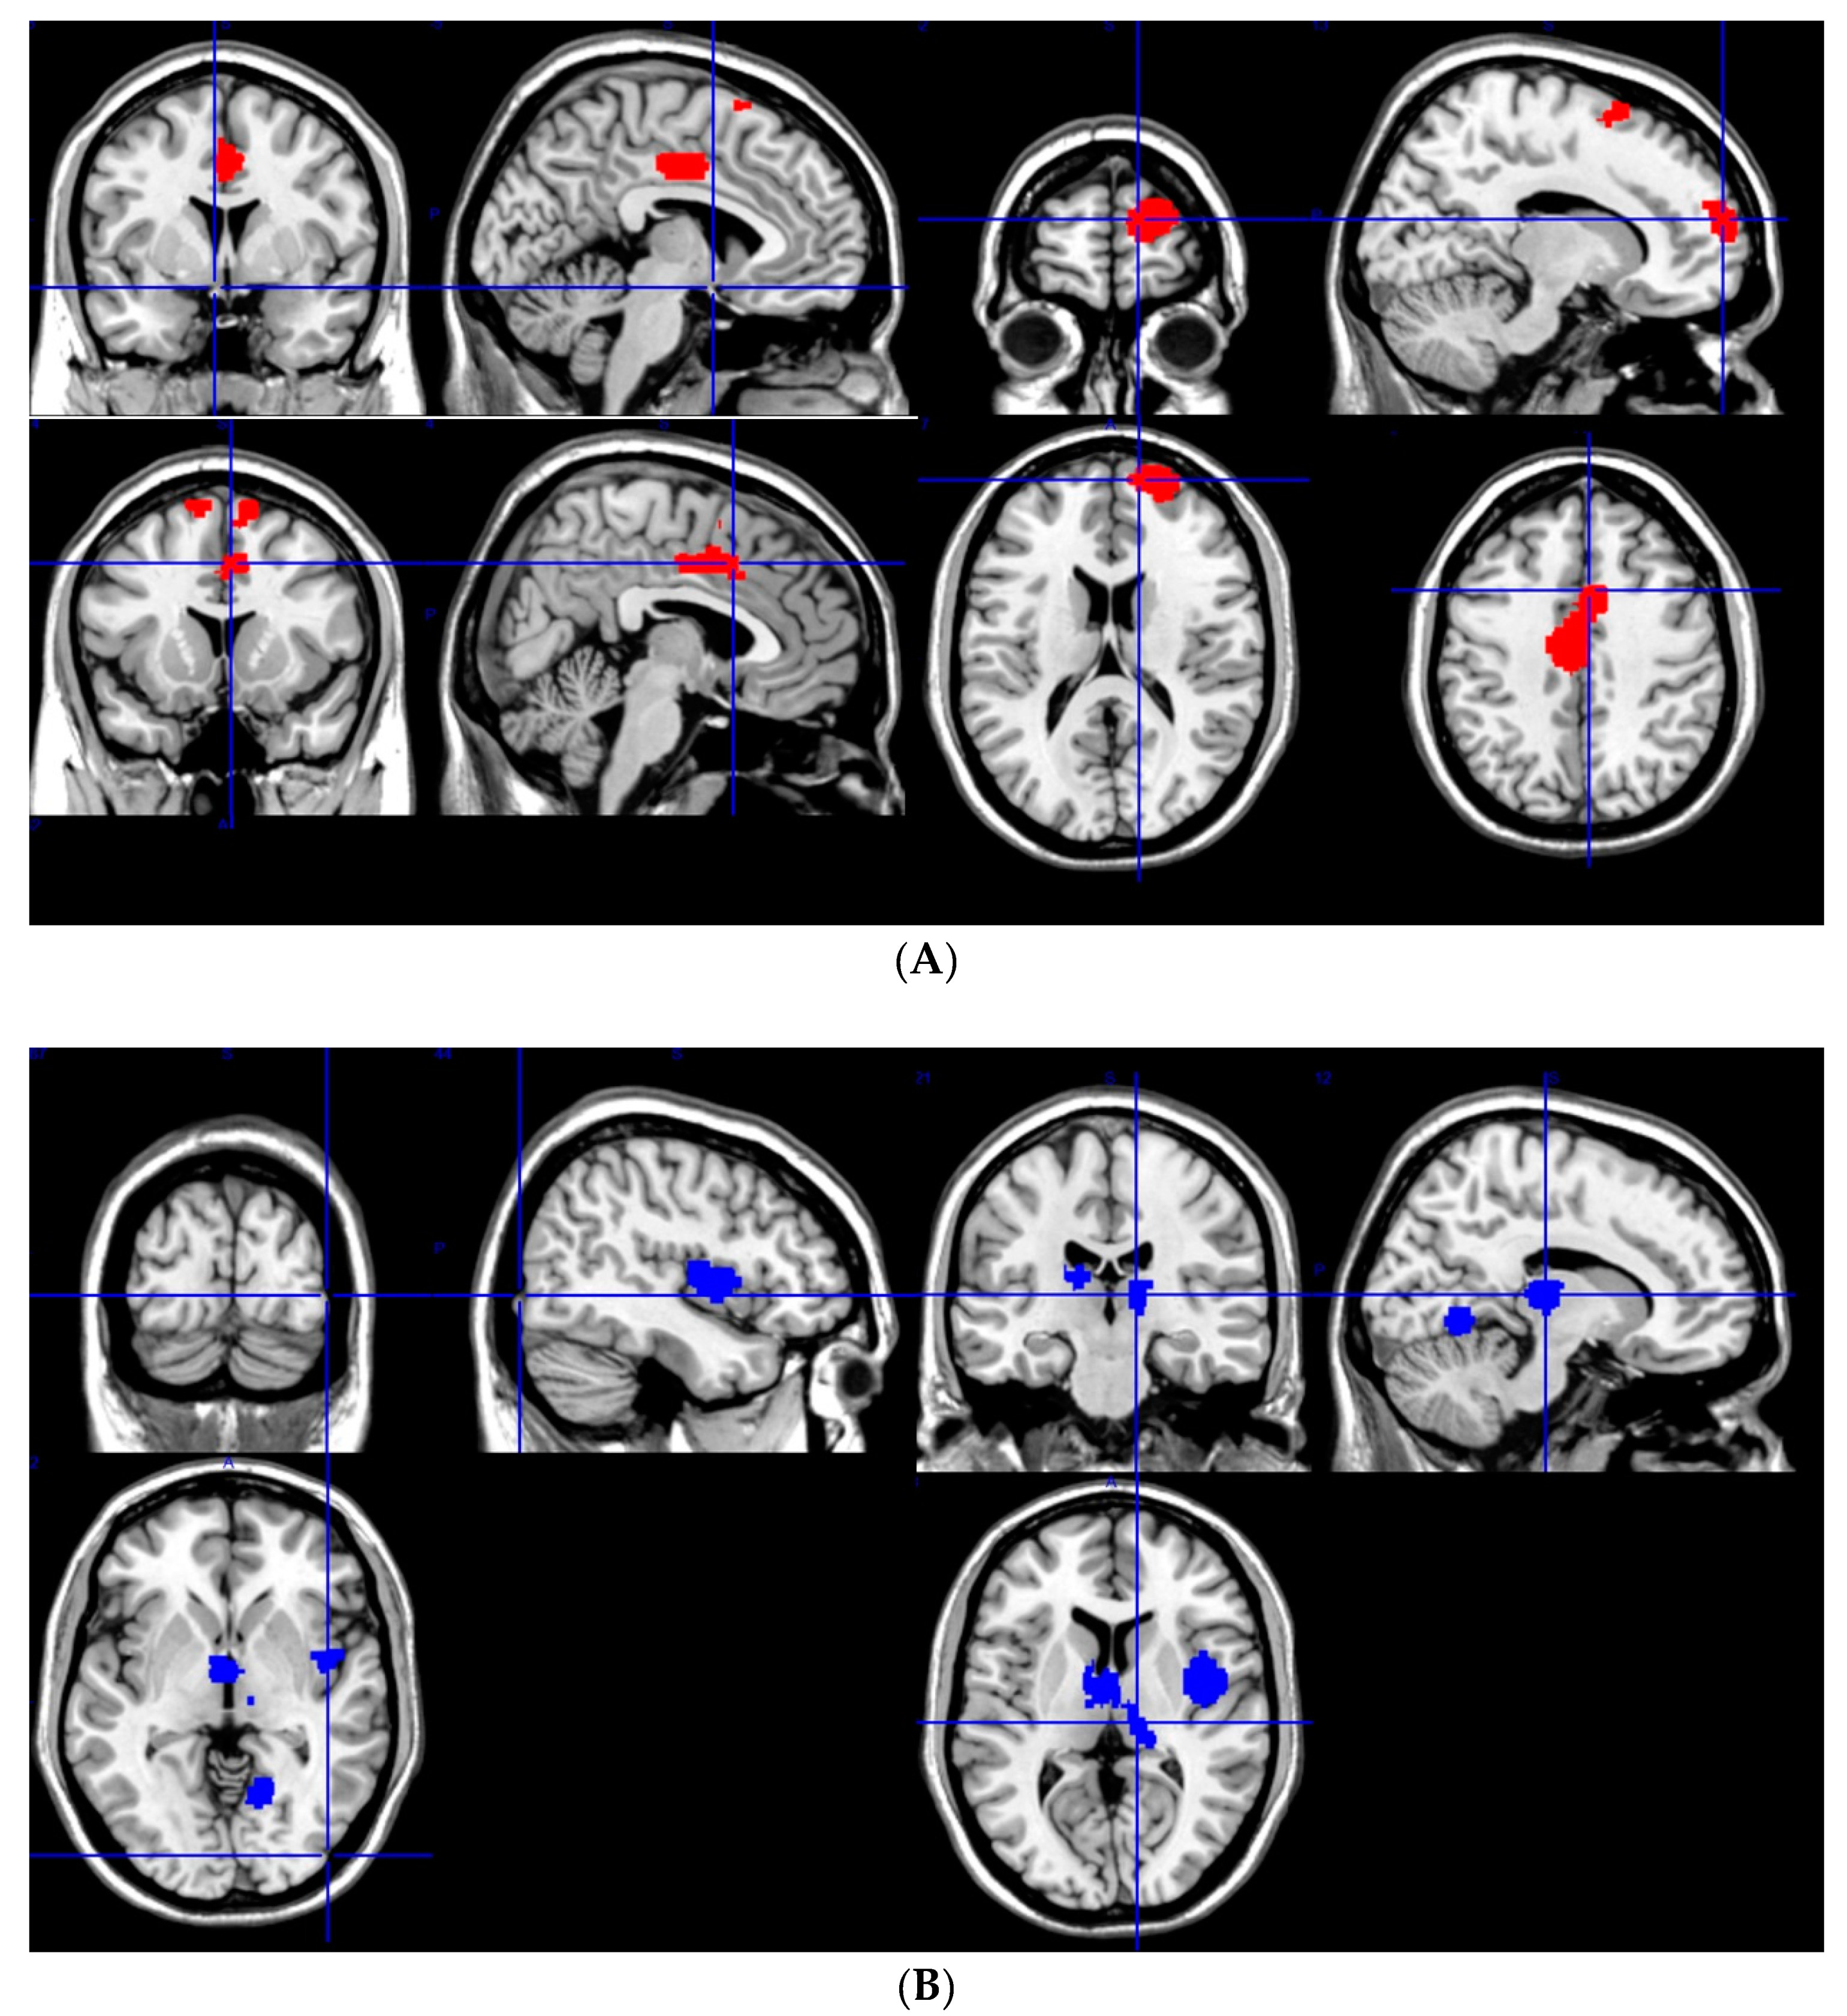

3.2.1. GM Increases

3.2.2. GM Decreases